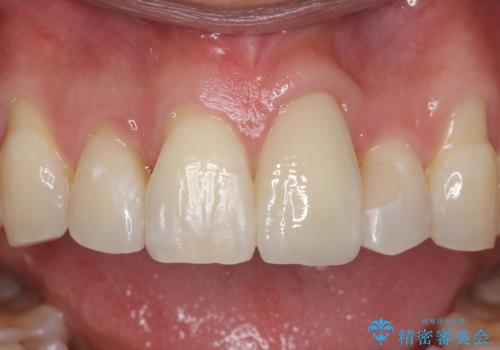

左上1はジルコニアクラウン(スペシャル)で治しました。スペシャルの場合は写真をとり、オリジナルの色味で作成することが可能です。

矯正治療前に虫歯を取り、歯並びが良くなってから本格的にセラミック治療を行いました。